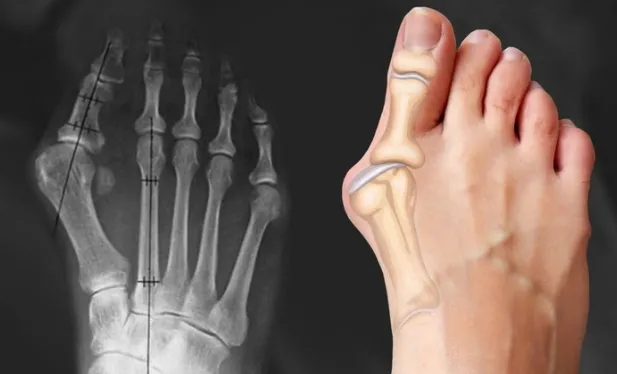

Избавьтесь от боли и прогрессирующей деформации стопы, используя техники артикуляционно-рефлекторного массажа. Автор курса показывает, как работать с «косточкой» (hallux valgus), плоскостопием и сопутствующими изменениями в структуре стопы и голени.

В основе материала лежит остеопатический подход, направленный на мягкое воздействие и коррекцию без травмирующих манипуляций. Курс объясняет не только технику массажа, но и анатомию нижней конечности, что позволяет работать с причинами патологии, а не только с внешними симптомами. Помимо профессиональных приемов, разбирается методика самокоррекции стопы при помощи специальных упражнений. Материал будет полезен как практикующим массажистам для расширения набора инструментов, так и тем, кто хочет освоить безопасные техники для помощи себе и близким.